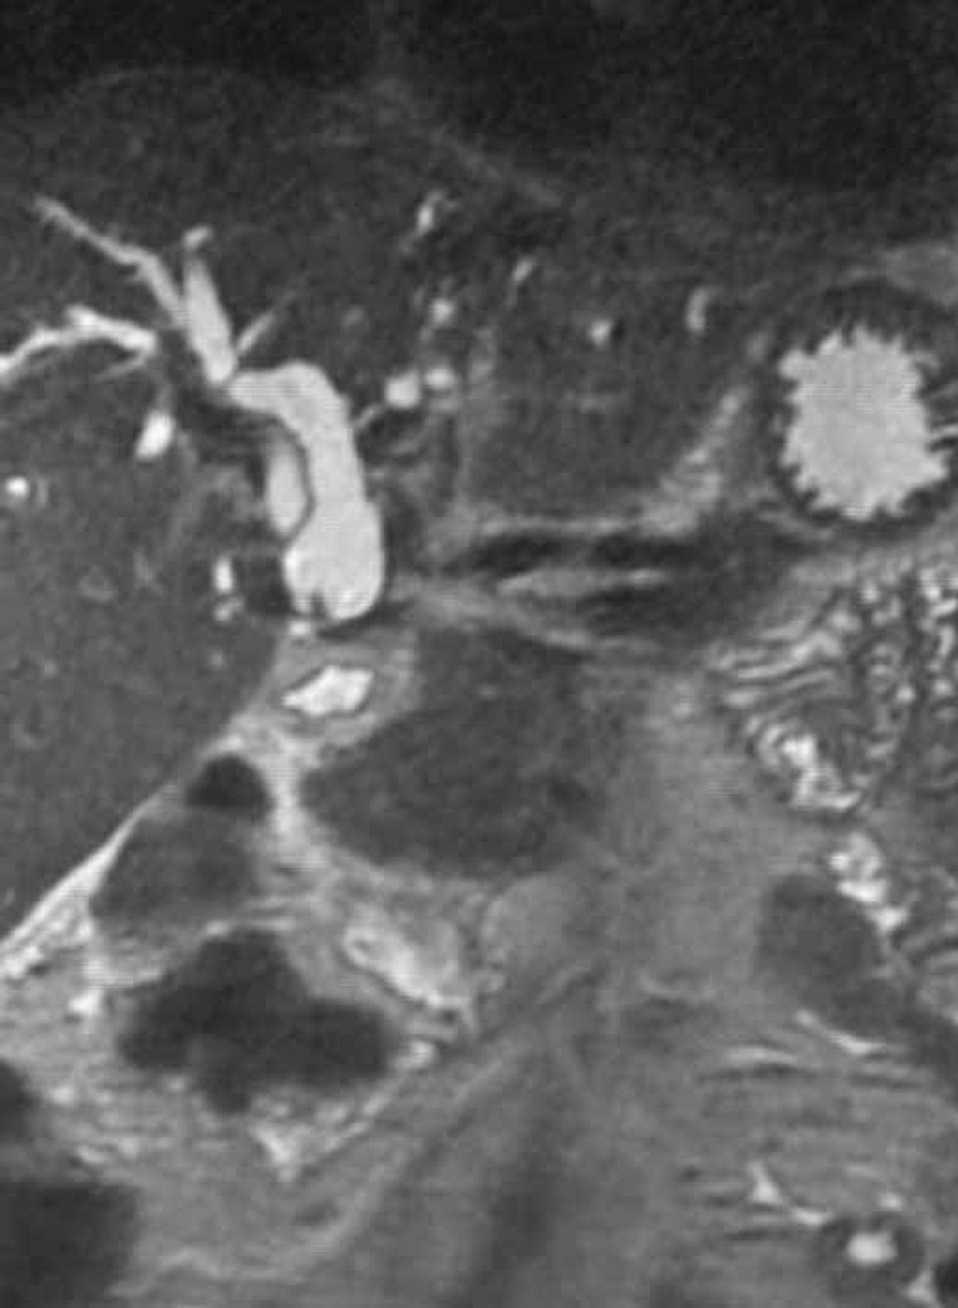

Fig. 2.

Varón de 40 años con antecedentes de cirugía laparoscópica en abril 2002 (intervención de Toupet y colecistectomía por colelitiasis). Acudió a urgencias en octubre de 2002 por un cuadro de fiebre, escalofríos e ictericia con coluria y prurito generalizado. En la exploración el paciente mostraba ictericia cutaneomucosa y dolor en el hipocondrio derecho a la palpación profunda, sin signos de irritación peritoneal. El estudio analítico demostró un patrón de colostasis (Bi 7,4 mg/dl, AST 299 U/l, ALT 525 U/l, FA 772 U/l, GGT 1141 U/l) y CA 19,9 144,51 U/ml. La colangiopancreatografía retrógrada endoscópica (CPRE) reveló una estenosis en la unión del conducto hepático común con los conductos hepáticos en probable relación con cirugía previa. La colangiografía por resonancia magnética (CRM) (figs. 1 y 2) mostró una estenosis importante en hepático común con dilatación de vía biliar intrahepática. En el interior de la vía biliar, por encima de la estenosis, se identificó una imagen de densidad disminuida, en probable relación con una coledocolitiasis. En la intervención quirúrgica se evidenció una estenosis de la vía biliar en la confluencia de los conductos hepáticos. Se realizó resección de la zona estenótica y hepaticoyeyunostomía en “Y” de Roux terminolateral transmesocólica. En el interior de la vía biliar se objetivó un endoclip embebido en una litiasis pigmentada (fig. 3). La anatomía patológica informó de segmento de vía biliar con una luz de 4 mm de diámetro, ausencia de epitelio y un infiltrado inflamatorio crónico y fibrosis de la pared. No había signos de malignidad. El postoperatorio transcurrió sin incidencias.